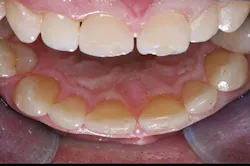

Occlusion-Bruxers, either grinders or clenchers, are not good indications for veneers. Properly placed crowns are a better choice (figure 3).

Figure 2: The two central incisors were treated with crowns, offering optimum strength and ability to contour the teeth equally.